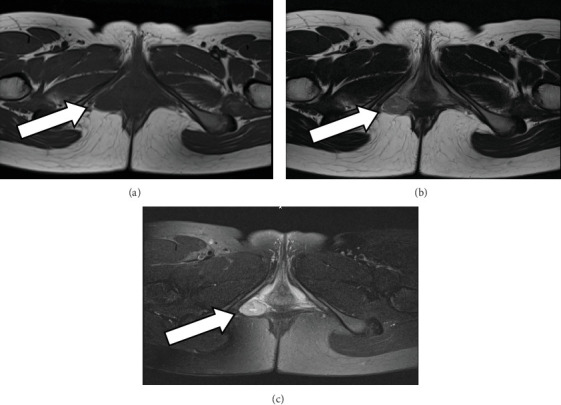

发生于外阴的平滑肌瘤非常罕见,很难与巴托林腺囊肿及侵袭性血管黏液瘤鉴别。我们报告一例外阴平滑肌瘤在一个少年女孩。患者,一名16岁的女性,曾注意到右外阴有一个柔软的皮下结节2年。起初,她怀疑是巴托林腺囊肿,医生给她开了抗生素。然而,由于持续的症状,患者被转介到我们的诊所进一步检查。MRI扫描怀疑为间充质瘤,并进行手术切除。肿瘤细胞抗平滑肌抗体、HHF35、Desmin弥漫性阳性,怀疑为平滑肌瘤。雌激素受体免疫染色阴性,孕酮受体免疫染色阳性。患者表现出良好的术后过程,在最近的随访中没有复发的迹象。手术切除是唯一有效的治疗方法,由于很少有复发的报道,建议长期随访。

Leiomyoma arising from the vulva is very rare, and it is difficult to differentiate it from a Bartholin gland cyst and aggressive angiomyxomas. We report a case of vulvar leiomyoma in a juvenile girl. The patient, a 16-year-old female, had noted a tender subcutaneous nodule on the right vulva for 2 years. At first, a Bartholin gland cyst was suspected, and she was prescribed antibiotics. However, because of persistent symptoms, the patient was referred to our clinic for further examination. An MRI scan suspected a mesenchymal tumor, and surgical resection was performed. Tumor cells were diffusely positive for anti-smooth muscle antibodies, HHF35, and Desmin, and leiomyoma was suspected. Immunostaining tests were negative for estrogen receptor and positive for progesterone receptor. The patient exhibited an excellent postoperative course with no evidence of recurrence at the latest follow-up. Surgical resection is the only curative treatment, and long-term follow-up is recommended because of rare reports of recurrence.